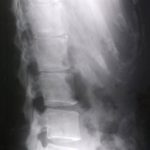

脊柱管とは脳から続く脊髄神経が通っている管のことです。

脊柱の管。

脊柱管狭窄症とは、この脊髄を通す管が何らかの原因で狭くなり、脊髄を圧迫して痛みやしびれなどの症状を出す疾患とされています。

和歌山在住の成人(21歳-97歳)1009名(男性335人、女性674人、平均年齢66.3歳)がレントゲン撮影により分析されました。

そのうち痛みなどの症状がある人は全体で9.3%(男性10.1%、女性8.9%)で、大多数の方はレントゲン画像上腰に脊柱管狭窄があっても無症状だったのです。

次に紹介する論文では、腰部脊柱管狭窄症の方100名をレントゲンや脊髄造影、CTで調べた結果、脊柱管の狭窄の程度と、痛みやしびれなどの症状は一致しなかったというものです。